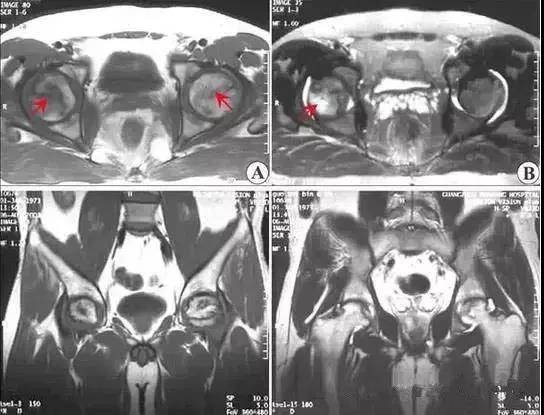

(3)股骨头坏死的 MRI 表现

MRI 敏感性优于骨核素扫描和 CT 及 X 线检查。这是因为股骨头发生坏死后,修复组织不断伸入坏死区上方骨髓的变化早于骨质变化,MRI可以在骨质塌陷及修复以前反映出骨髓细胞的变化。所以, MRI 应作为早期检查诊断骨坏死的主要手段。

Ⅱ期

股骨头不变形,关节间隙正常。T 1加权为新月形边界清楚的不均匀信号,T 2加权显中等稍高信号,周围不均匀稍低信号环绕,呈典型的双线征,位置基本与CT的条状骨硬化一致。病理上为病灶中心大量不规则的细胞碎片坏死,周边纤维化,新骨形成和肉芽组织增生。

4.jpg

上图为II期